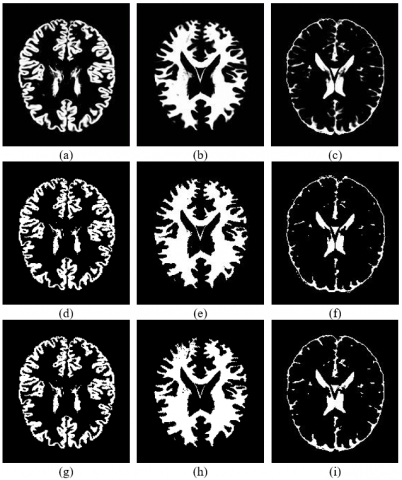

Figure 5 shows the results of the PFCM algorithm applied to segment several brain images. Column 1 presents the original ADNI dataset images, Column 2 shows the extracted CSF regions, Column 3 shows gray matter extraction images, and Column 4 shows white matter extraction for the brain images in the ADNI dataset. Because the image sizes for the ADNI datasets vary significantly, they are resized to 512×640 pixels as part of the pre-processing step. The post-processing step involves converting the final segmented regions to black and white to facilitate comparison with the ground truth.

The segmentation results of the proposed algorithm are shown in Figure 6. Row 1 illustrates the ground truth for gray matter, white matter, and CSF. Row 2 shows GM, WM, and CSF extraction using PFCM, while Row 3 shows the same extraction method using GRIFCM. According to a subjective evaluation, the proposed method effectively extracts brain tissue. The segmentation results of the proposed algorithm are displayed in Figure 7. Based on subjective evaluation, the proposed method proves effective for brain tissue extraction.

Figure 5. (a) very mild (e) mild (i) moderate images from ADNI data set, (b)(f)(j) CSF extracted, (c)(g)(k) gray matter extracted (d)(h)(l) white matter extracted

Figure 6. Segmentation results of proposed algorithm (row 1) ground truths of GM, WM, and CSF, (row 2) GM, WM, and CSF extracted using PFCM (row 3) GM, WM, and CSF extracted using GRIFCM [14]

Figure 7. Segmentation results of proposed algorithm PFCM for normal, moderate, and mild Alzheimer's images